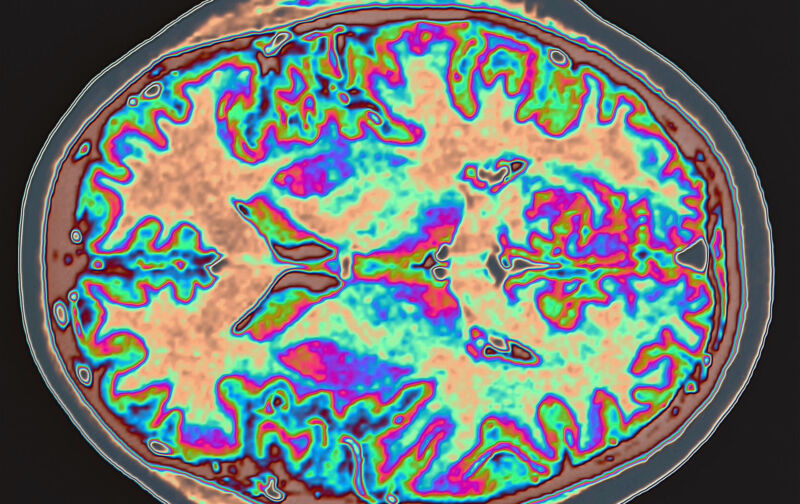

Figuring out exactly what the virus does inside the human body is likely to take years. But we got a bit of data this week from a detailed study of images of the brains of COVID patients. The images were taken before and after the patients were infected. The results suggest some regions of the brain connected to the olfaction system may shrink slightly in the wake of an infection, although the effect is minor and its consequences are unclear.